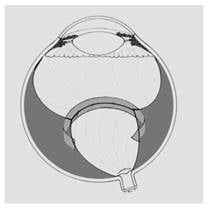

Página 323 - 9.3. Evolución de la ROP